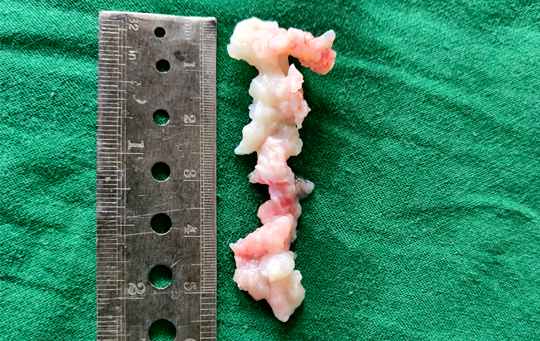

Lumbar radiculopathy is often caused by a prolapsed disc causing low back pain with radiation to the leg/s. Pain may be associated with tingling, numbness, pins and needles like sensation and weakness of the leg/s. In most cases, the symptoms ease off gradually over several weeks with analgesics, good physiotherapy and normal activities. Surgery is an important option if the symptoms persist or progress.